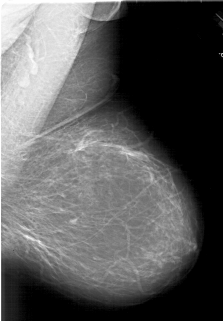

A_1846_1.LEFT_MLO

LEFT_MLO LINES 6751 PIXELS_PER_LINE 4801 BITS_PER_PIXEL 12 RESOLUTION 43.5 OVERLAY

FILE: A_1846_1.LEFT_MLO.OVERLAY

TOTAL_ABNORMALITIES 1

ABNORMALITY 1

LESION_TYPE MASS SHAPE LOBULATED MARGINS ILL_DEFINED

ASSESSMENT 4

SUBTLETY 2

PATHOLOGY BENIGN

TOTAL_OUTLINES 1

BOUNDARY